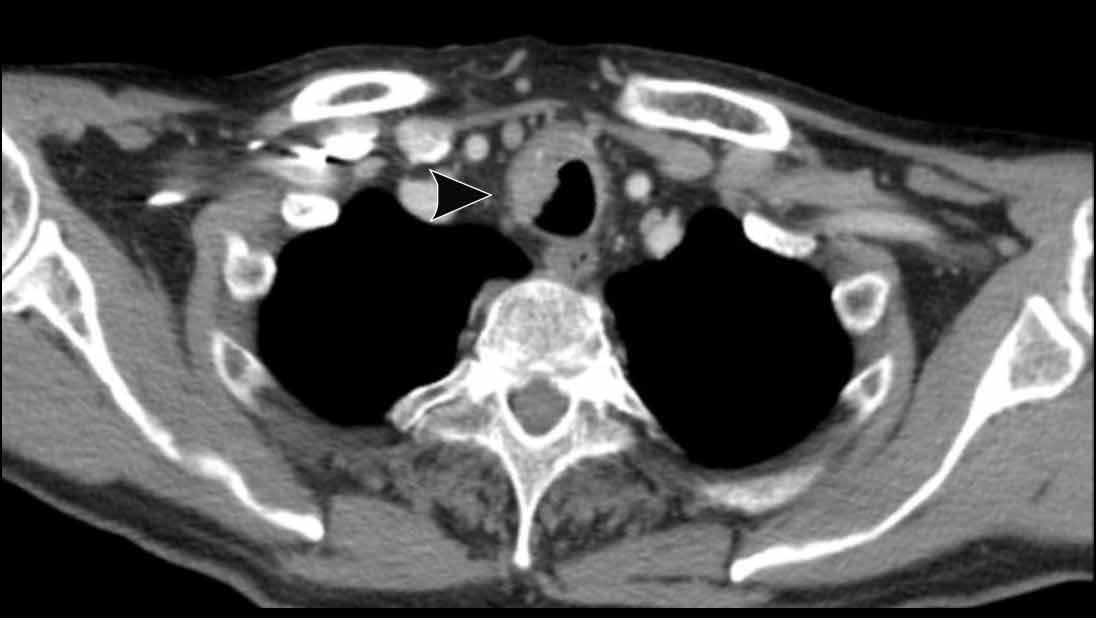

Hạch bạch huyết

Chèn ép phế quản chính phải do hạch bạch huyết to.